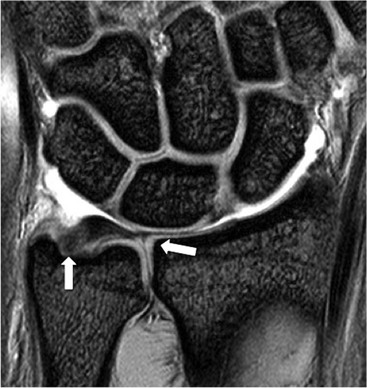

The TFC is composed of fibrocartilage and is normally low SI on all MRI pulse sequences (Fig. 46-31). Tears of the TFC complex may present as ulnar-sided wrist pain. They occur as either a degenerative phenomenon or as an acute injury. Degenerative tears frequently result in central perforation of the TFC (Fig. 46-32), and are associated with positive ulnar variance (long ulna). This in turn may lead to ulnar abutment on the triquetrum, which is another cause of ulnar-sided wrist pain.

Traumatic TFC tears often affect the ulnar attachments and are associated with ulnar styloid fractures (Fig. 46-33). These injuries may also involve the dorsal and volar radioulnar ligaments and can lead to DRUJ instability.